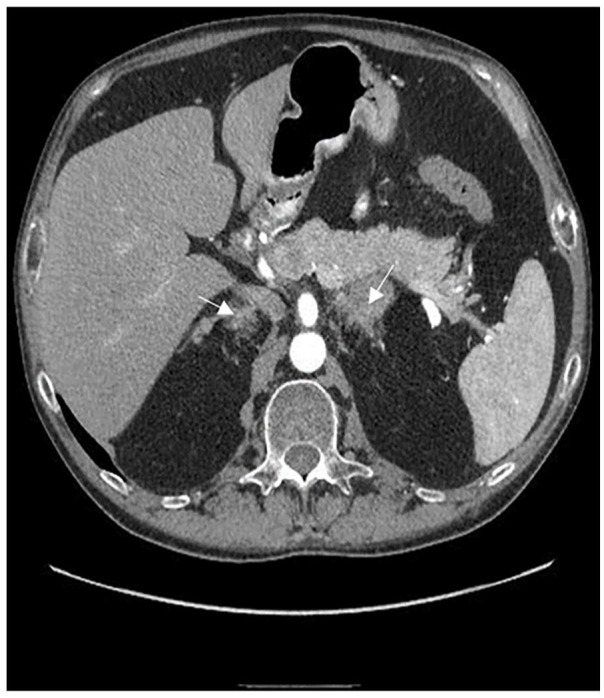

卡尼综合征(CNC)是一种罕见的综合征,其特征是皮肤色素斑和多种肿瘤,尤其是心肌瘤、分裂瘤和内分泌肿瘤。该病通常为常染色体显性遗传,大多数病例都存在 PRKAR1A 基因突变。男性不育是 CNC 表型的一部分,主要与大细胞钙化性 Sertoli 细胞瘤(LCCSCT)有关。我们描述了一例 30 岁的男性卡尼综合征患者,该患者表现为严重少精症和原发性色素结节性肾上腺皮质疾病(PPNAD)。在随访过程中,严重少精症和精液运动能力受损的情况持续存在,患者还被诊断出患有复发性心脏肌瘤和 LCCSCT。分子检测发现了一种新型 PRKAR1A 突变,涉及外显子 4 至 7 的缺失。我们的研究结果表明,无论是否存在睾丸肿瘤,该突变都会导致 PRKAR1A 单倍体缺乏,这可能与男性不育直接相关。因此,在患有 CNC 的男性患者中,PRKAR1A 基因突变的检测可作为不育症的预测指标。本病例报告说明了早期考虑和处理 CNC 男性患者不育症的重要性。

Carney Complex (CNC) is a rare syndrome characterized by spotty skin pigmentation and multiple neoplasms, notably cardiac myxomas, schwannomas, and endocrine tumours. It is often inherited in an autosomal dominant manner with PRKAR1A gene mutations found in the majority of cases. Male infertility is established as part of the CNC phenotype and is largely associated with Large cell calcifying Sertoli cell tumours (LCCSCT). We describe a case of a 30-year-old male patient with Carney Complex, presenting with severe oligoasthenozoospermia and primary pigmented nodular adrenocortical disease (PPNAD). During follow-up consults, the severe oligozoospermia and impaired semen motility persisted and the patient was also diagnosed with a recurring cardiac myxoma and LCCSCT. Molecular testing identified a novel PRKAR1A mutation involving a deletion of exons 4 to 7. Our findings suggest this mutation causes PRKAR1A haploinsufficiency, which may be directly linked to male infertility, irrespective of the presence of testicular tumours. Accordingly, in male patients with CNC, detection of a PRKAR1A gene mutation may serve as a predictive marker for infertility. This case report illustrates the importance of early consideration and management of infertility in male patients diagnosed with CNC.